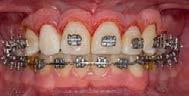

De frente (Figura 7) presenta líneas medias dentales no coincidentes, 6 mm overjet, 10% overbite, relación molar y canina clase II bilateral. Las oclusales (Figura 8) la arcada superior de forma triangular, presencia de OD 53 y apiñamiento severo, la arcada inferior de forma cuadrada con segundos molares en erupción y apiñamiento moderado.

Se indicó la extracción del OD 53, 12 y 24, el OD 14 ocupa el lugar del OD 13. Para la corrección del apiñamiento maxilar y mandibular con la alineación y nivelación dental iniciando con

un bondeo seccional superior del OD 17 al 14, del 27 al 23, bondeo de 6 a 6 en inferior, secuencia de arcos: Niquel Titanio 0.014", 0.016", 0.018", 0.017 × 0.025", 0.019 × 0.025" superior e inferior. Para obtener la clase I canina bilateral mediante cierre de espacio y distalización del OD 23 acompañada de mecánica de elásticos vector clase II bilateral 3/16 4.5 oz. Para conseguir la clase II molar funcional a través de elásticos intermaxilares vector clase II 3/16 4.5 oz. Se esperó la erupción pasiva del OD 13 en la posición del incisivo lateral derecho.